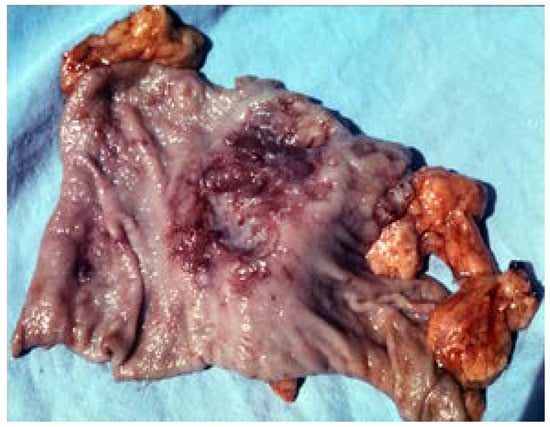

2. Giant Ulcers (over 2–3 cm)